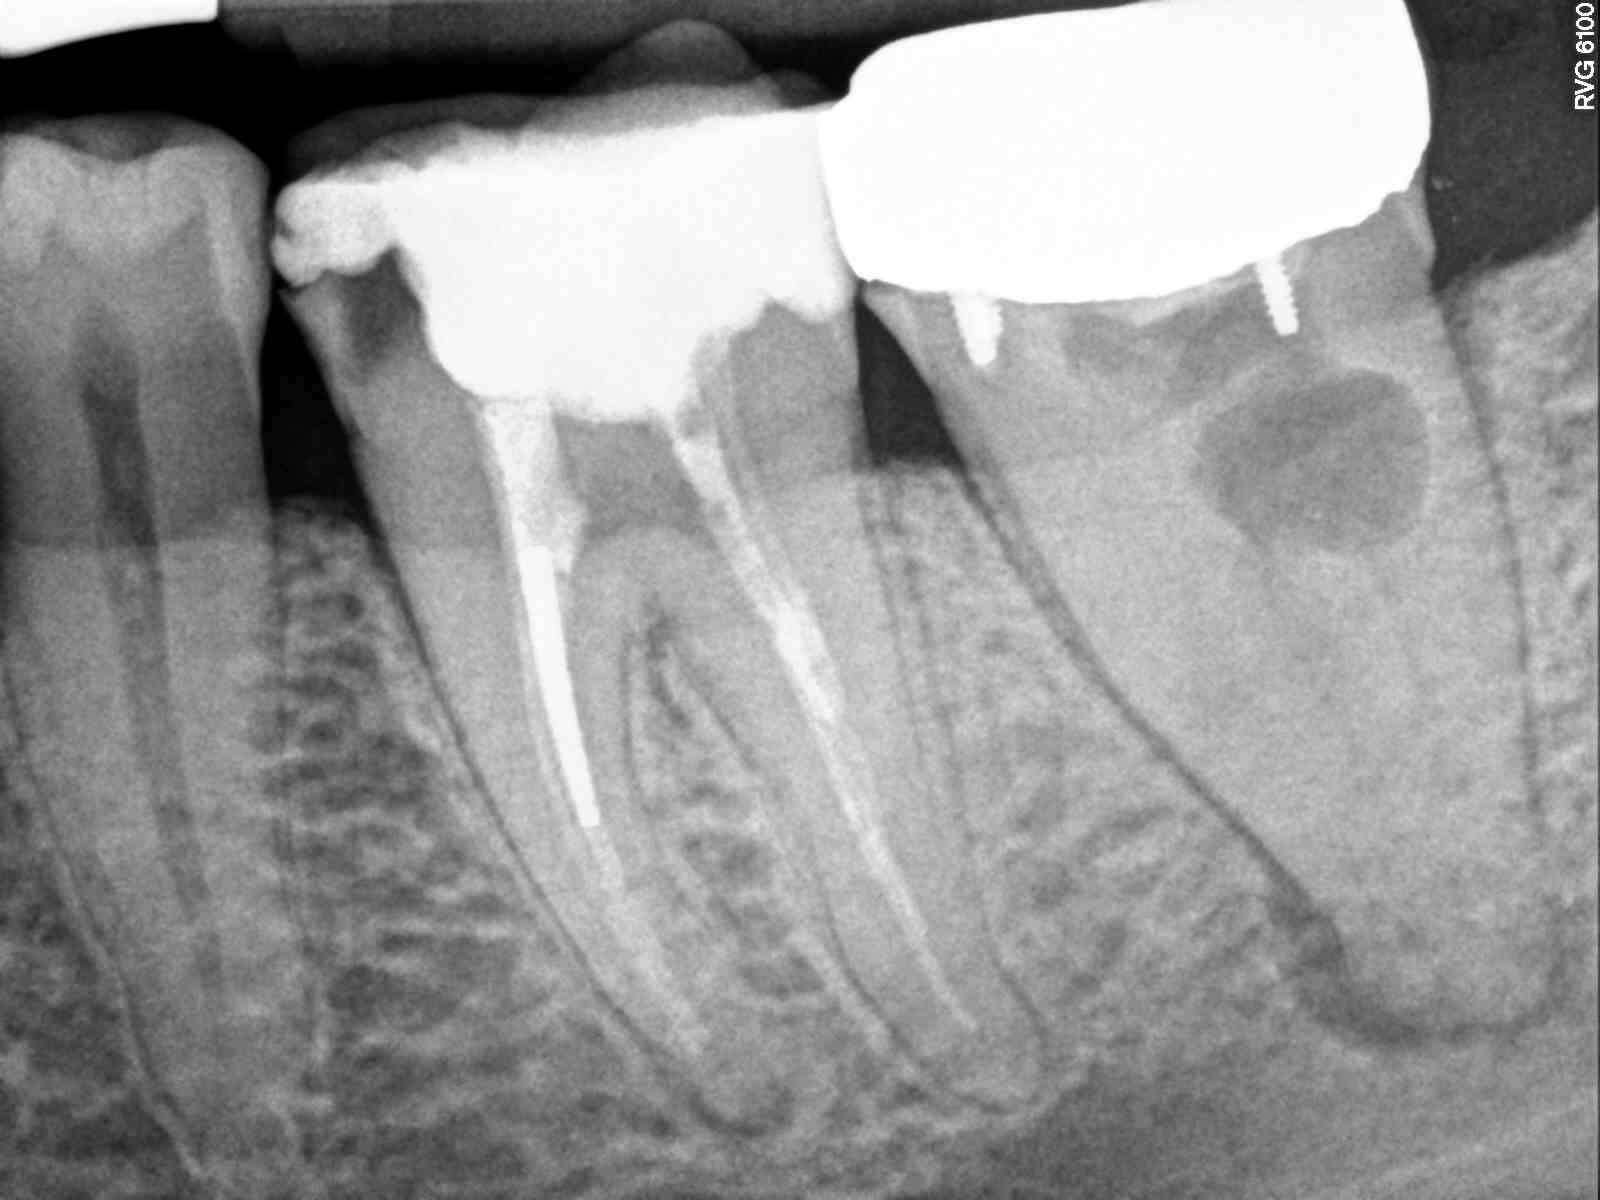

Endodontic Retreatment Columbia River Endodontics Endodontic Treatment Reasons an endodontist is a dentist who specializes in the causes, diagnosis, prevention, and treatment of diseases and. while many feel uneasy about the idea of a root canal, the procedure is a safe and straightforward way to remove diseased pulp tissue and is a better. common reasons for root canal therapy include: This may be necessary when. Endodontic Treatment Reasons.

REASONS FOR VISITING DENTIST Dental Retreatment (part 1) Root Canal Endodontic Treatment Reasons 100k+ visitors in the past month This may be necessary when a root canal isn't enough to save your tooth, calcium deposits in. endodontic treatment is necessary when the pulp, the soft tissue inside the root canal, becomes inflamed or infected. an endodontist is a dentist who specializes in the causes, diagnosis, prevention, and treatment of diseases and.. Endodontic Treatment Reasons.

Endodontic Root Perforation Causes, Identification, and Management Endodontic Treatment Reasons there are many clinical reasons for needing root canal treatment, but there are also countless practical reasons why saving. Repeated dental procedures on the tooth. Repeated dental procedures on the. This may be necessary when a root canal isn't enough to save your tooth, calcium deposits in. common reasons for root canal therapy include: endodontic treatment is. Endodontic Treatment Reasons.